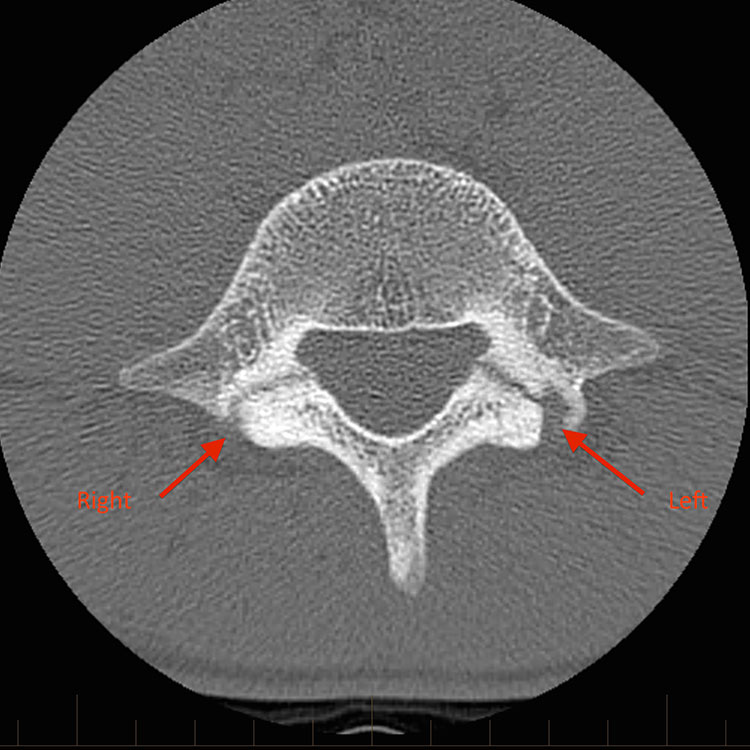

2. CT (Computed Tomography)

• x-ray로 쉽게 시각화 되지 않는 주상골, pars interarticularis 척추관절간부와 같은 뼈의 피질 골절을 시각화하는 데 필요할 수 있다.

• 주상골 피로골절의 진단 및 병기 결제 있어 황금표준으로 간주 된다.

• 척추분리증의 골절선 유무 및 완전성을 추가로 확인하기 위해 표적 CT가 필요할 수 있다.